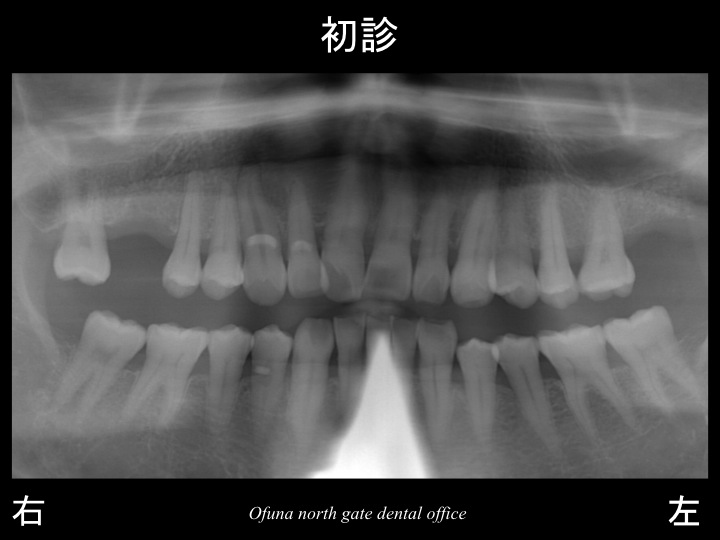

患者様は、上顎の左右の奥歯を他歯科医院で抜歯されたため、噛めないとのことで当医院を受診されました。

以下のレントゲンが初診時になります。

以下の●:赤丸が歯がない部分になります。